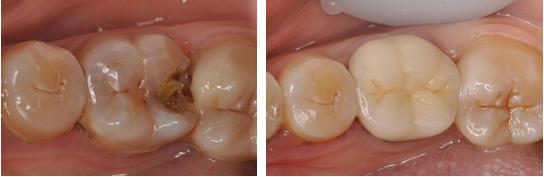

2. 嵌体修复:根据牙齿缺损部位窝洞的形状,用全瓷制作出来相应的修复体,粘结在缺损部位。

适应症: 各种牙体缺损较为严重,嵌体修复耐磨,不脱落无需二次充填,使用年限较长,多用于后牙修复。

修复技术:瓷嵌体